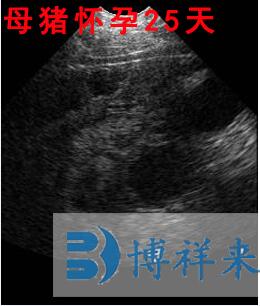

母猪25天在猪用B超图像特点: 妊娠25 d探查到多个没有规则形状的孕囊,子宫区域内显示两个相邻孕囊及其中的胎体反射。